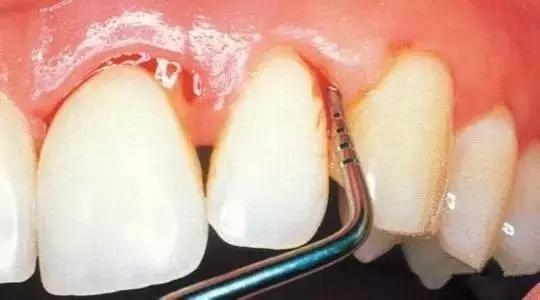

(窝沟封闭过程)